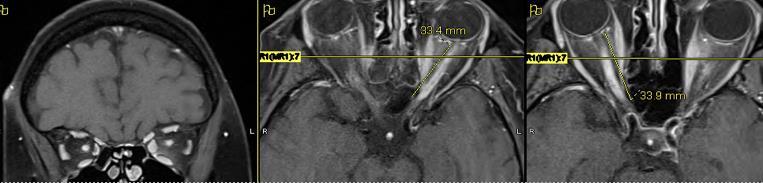

NMO: visual parameters and outcomes

MRI lesions

comparing with MS: More extended bilateral Chiasma

Comparing with MS: bilateral, VA lower, OCT lesions more severe (RNFL, GCL)